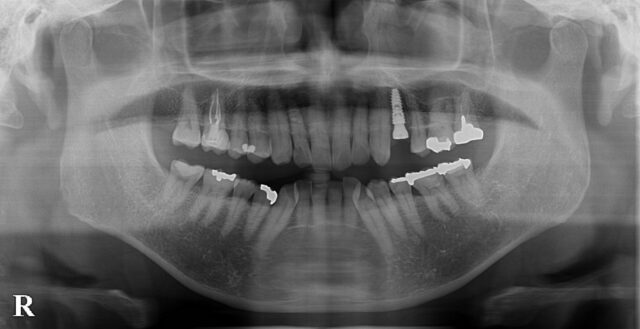

術後(パノラマ写真)

術前 術後